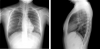

Antecedentes de HTA. Consulta por dolor cervical intenso hasta precisar tratamiento con opioides de cinco meses de evolución.En los últimos tres meses progresiva debilidad en las extremidades,sin poder caminar sin ayuda,estreñimiento e incontinencia urinaria. Exploración...

Neurología: Patología de raquis | InfecciosasEtiología: Infecciosas / inflamatoria / desmielinizanteDiagnóstico final: Compresión medular secundaria a tuberculosis diseminada.Nivel de certeza: